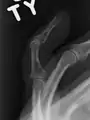

انگشت چکشی یا مالت فینگر (به انگلیسی:Mallet Finger) یک نوع آسیب عضلانی است که در اثر پارگی تاندون بند آخر (تاندون بازکننده انگشت) ایجاد میشود. از نشانههای این آسیب افتادن بند آخر انگشت مربوطه و عدم توانایی فرد آسیبدیده در صاف نگه داشتن آن میباشد.[1] در صورت درمان نکردن فرد مبتلا مجبور به جراحی می شود

| انگشت چکشی. | |